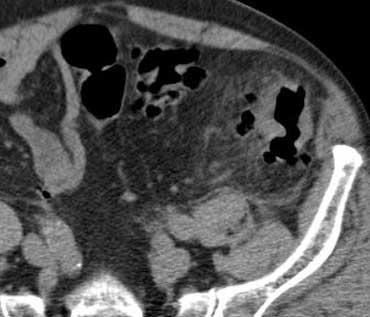

Tắc ruột cơ học. CT cho thấy các quai ruột non giãn, trong khi một phần ruột non và toàn bộ đại tràng không giãn. Do đó đây phải là tắc ruột non cơ học, và trong trường hợp này nguyên nhân có thể xác định dễ dàng: lồng ruột (đầu mũi tên).

Trước tiên, xác định phần nào của ống tiêu hóa bị ảnh hưởng: ruột non, đại tràng, hay cả hai.

Tìm kiếm các quai ruột bình thường không giãn; nếu có, dấu hiệu này gợi ý mạnh mẽ nguyên nhân tắc nghẽn cơ học.

Chẩn đoán tắc ruột non được xác lập khi thấy đồng thời các quai ruột non giãn và các quai ruột non xẹp.

Khi xác định có tắc nghẽn, cần cố gắng xác định nguyên nhân và vị trí tắc (dính ruột, u, xoắn ruột, lồng ruột, thoát vị bẹn).

Dính ruột chiếm 60-80% tổng số các trường hợp và là nguyên nhân có khả năng nhất khi thấy hình ảnh chuyển tiếp trơn tru từ quai ruột non giãn sang quai ruột non xẹp.